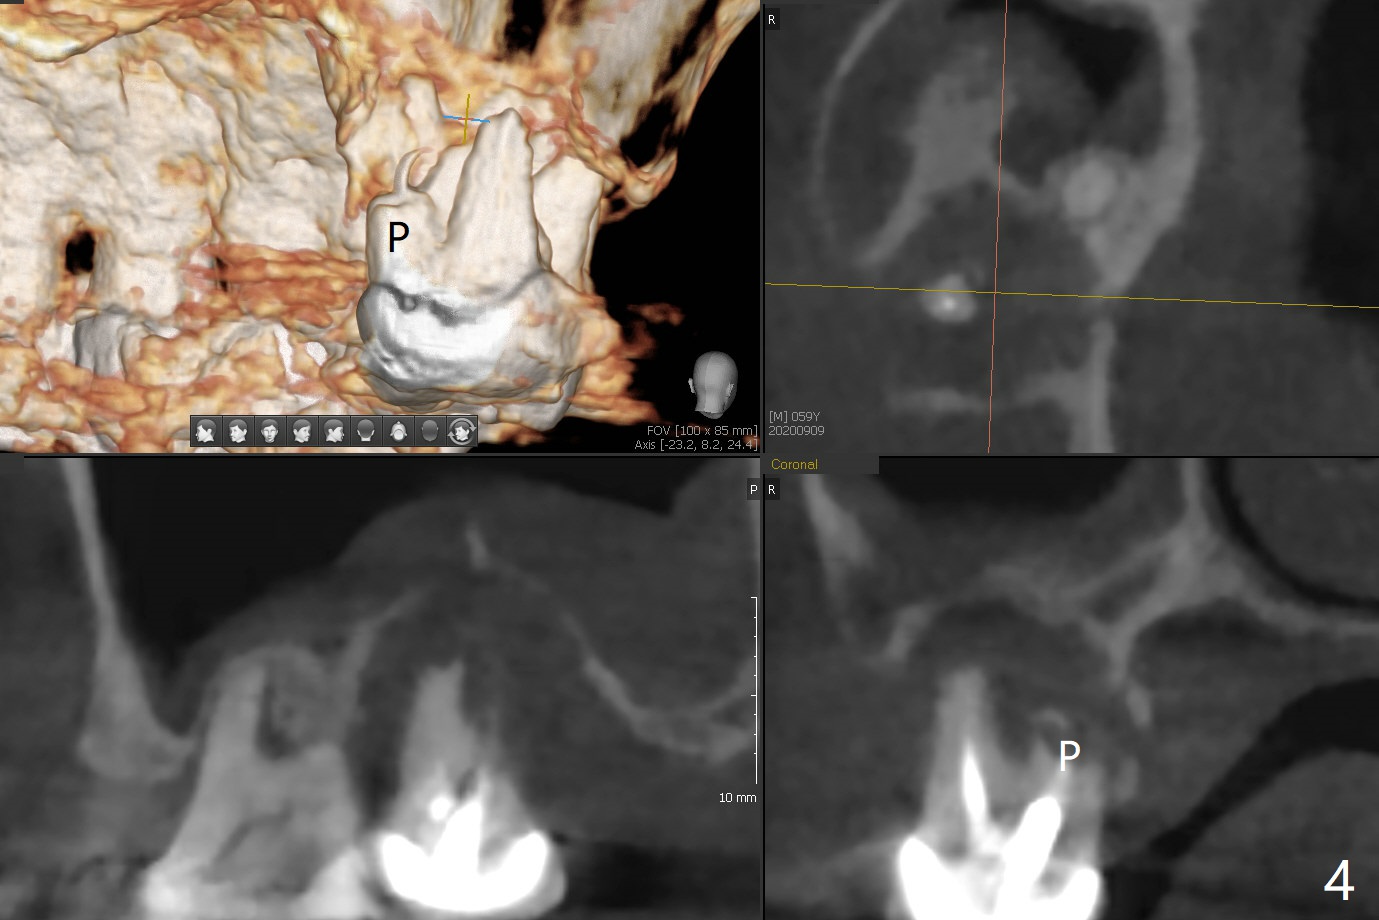

59岁女右上七骨质吸收严重(图一),上颌窦底板薄(图二:*),而窦膜厚(图三:*),应该容易提升,腭侧根吸收(图四:P),上颌窦底板穿孔(图五:*),拔牙后(图六:黑色),水提升(白箭头),放置PRF膜(黄色曲线)和粘性骨块(红色圆圈),最后完成位点保留(图七:大圆圈),放置另外一块PRF膜和6个月吸收膜,缝合,牙周或者树脂敷料。Return to No Deviation 19-21 位点保留后 导板与张口度 Xin Wei, DDS, PhD, MS 1st edition 09/09/2020, last revision 01/01/2021